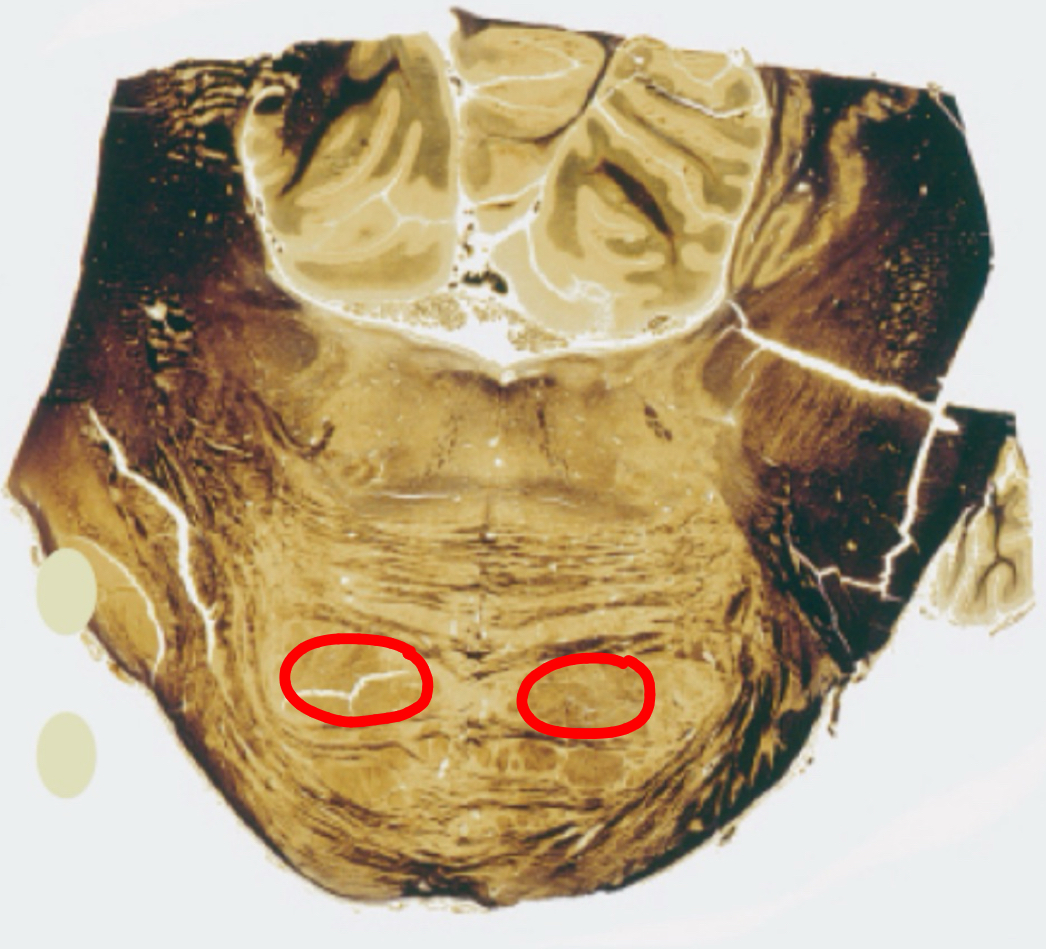

gracile tract caudal medulla II

gracile nucleus caudal medulla II

cuneate tract caudal medulla II

cuneate nucleus caudal medulla II

spinal tract of trigeminal caudal medulla II

trigeminal sensory nucleus

pyramids caudal medulla II